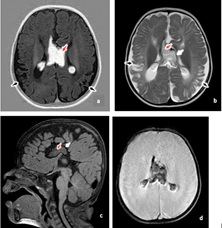

Figure 4 Alexander disease.

T2-weighted (a, b) and FLAIR (c) axial images showing diffuse cerebral atrophy with and bilateral symmetrical cerebral white matter high T2/FLAIR signal changes predominantly involving the periventricular white matter extending up to subcortical U fibers (posterior > anterior). Diffuse thinning of corpus callosum is noted on sagittal T1-weighted image (d). FLAIR, fluid-attenuated inversion recovery.